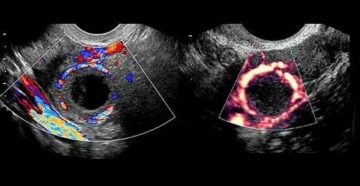

Киста яичника на УЗИ Яичники — это парные органы, имеющие огромное значение при зачатии. Именно…